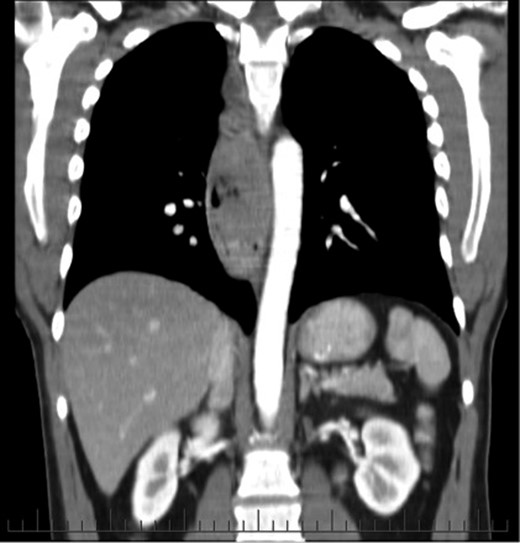

His initial endoscopy showed a 12 cm fungating, pigmented tumour occupying most of lower oesophageal lumen (Fig. 1). The biopsy was highly suggestive of primary malignant melanoma. Staging computed tomography (CT) and positron emission tomography (PET) showed extensive mediastinal, left supraclavicular and coeliac lymph node enlargement (FDG avid) with no evidence of metastatic disease (Fig. 2).

An endoscopic view of the fungating melanoma involving most of the oesophageal lumen.